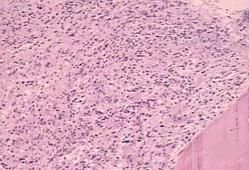

血小板由於體積小,特別是容易發生粘附、聚集和變性破壞,故常難以準確計數,常藉助於高科技血液分析儀。血小板計數方法主要有兩大類:血細胞分析儀法和目視顯微鏡計數法。目視顯微鏡技術法有普通光學顯微鏡計數法(分為直接法和間接法,但後者已被淘汰)和相差顯微鏡法。

相差顯微鏡直接計數法

用草酸銨作稀釋液,在明顯的顯微鏡下進行計數,並可於照相後核對計數。此法準確性高,血小板易於識別。